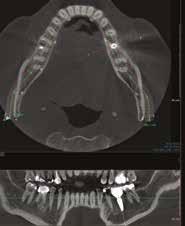

A-PRF membránokkal borítottuk (7. ábra). A mukogingivális lebenyt – annak megnyújtása nélkül – a helyére fektettük és varratokkal rögzítettük, per primam sebzárást nem végeztünk (8., 9. ábra). A varratokat 2 hét után távolítottuk el, a varratszedésig a sebgyógyulás támogatására per os 1000 mg/nap C- és 12 000 NE/nap D-vitamint adtunk (20). A műtéti beavatkozást 24 hét gyógyulási időszak követte, melynek során sem helyi, sem gyógyszeres kezelés nem történt, az esztétikum javítása érdekében a páciens ideiglenes kivehető fogpótlást használt. A csontos gyógyulás ellenőrzése és az implantáció tervezése céljából állcsonti CT felvételt készítettünk, illetve lenyomatvételt végeztünk. A CT felvételen tökéletes csontos gyógyulást észleltünk, az alveolaris csont volumene teljes mértékben megtartott volt (10. ábra), a klinikai kép is ennek megfelelően alakult (11., 12. ábra)

A Trishape Implant Studio™ a korábbi csont augmentáció területén, a felső állcsontnál áltagosnak számító D2-D3 csontminőséget jelzett (13. ábra). A lenyomat alapján készített gipszmodellt szkennelve virtuális mintát nyertünk. A CBCT felvétel és a virtuális modell adatait a Dual Scan protokoll (21) elveinek megfelelően használtuk fel az implantációs sablon (New Age Dental Kft, Nemeskéry Károly) készítéséhez (14., 15., 16. ábra). Az implantátum (Ankylos C/X A11) behelyezése teljesen navigált módon, 35 Ncm primer stabilitással történt (17., 18. ábra). Az implantátumra a fogtechnikus (D1 Dental Kft., Garamvári Csaba) által előzetesen